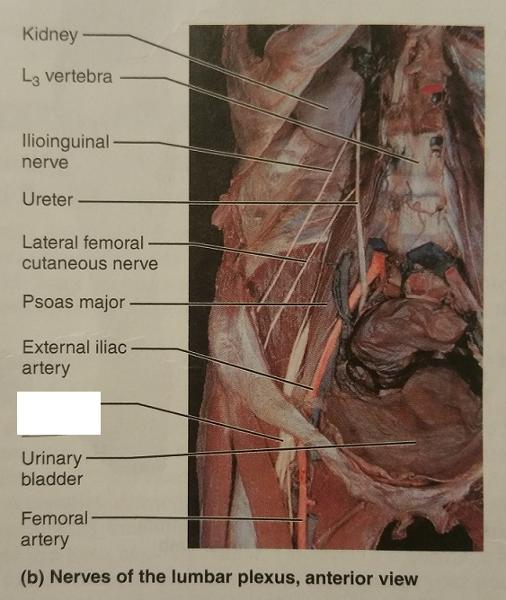

The lumbar plexus arises from the ventral rami of what lumbar nerves (and sometimes which thoracic nerve)?

L1-L4 and sometimes T12

The nerves of the lumbar plexus serves which region and which body part?

Serves the lower abdominopelvic region and the anterior thigh

What is the largest nerve of the lumbar plexus?

Femoral nerve

The femoral nerve arises from the ventral rami of what lumbar nerves?

L2-L4

The femoral nerve innervates which group of muscles? (Give an example)

Anterior thigh muscles

Ex. Sartorius muscle

The cutaneous branch of the femoral nerve also serves what general feature of which general body part?

Supply the skin of the anteromedial surface of the entire lower limb

Identify the blanks.

Identify the blanks.

Identify the blanks.

Identify the blanks.

Identify the blanks.

Identify the blanks.

Identify the blanks.

Identify the blanks.

Identify the blanks.

Identify the blanks.